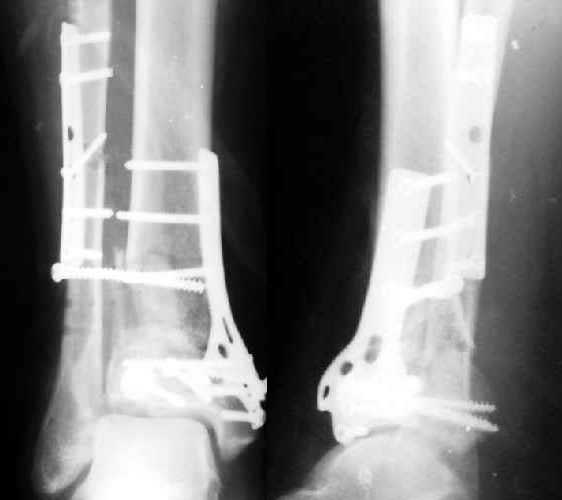

Полтора месяца назад мужчине 45 лет выполнена открытая репозиция дистального отдела большеберцовой кости и внутренняя фиксация (снимок 1).

На другой ноге - переломы нескольких плюсневых костей. Из-за сопутствующих урологических проблем через две недели перевели в другое учреждение, там был вынужден ходить с костылями с нагрузкой на обе ноги.При контрольной явке к нам через месяц обнаружилась несостоятельность фиксации (снимок 2). Какие выходы их положения можно тут предложить?

This is a BIG problem, that fortunately is somewhat less common now than 10 years ago. The fibula and a large piece of distal lateral tibia are now displaced laterally about 1 cm. It is difficult to assess how well reduced the tibia articular surface was and is. You might consider:

4. What is the status of the reduction. Again, syndesmosis very wide but other (fibular length, tibia articular surface, tibia alignment, talus beneath plafond) seems OK.

Yes. Looks like pure depression of the grafted metaphyseal part. Of course along with separation of the lateral aspect (plus syndesmosis and tibia).

Отправитель: Tom DeCoster 06 Август 2003, 14:38

It sounds like we are of similar opinion on this case. I didn't notice the collapse of the metaphyseal bone graft and talar tilt but upon re-review of the radiograph I see what you mean. I haven't had ANY luck successfully repairing this situation. Half the time it still doesn't look right on the post op x-rays (?perhaps inadequate surgeon-me). Half the time it collapses later and the other half (sic) it doesn't matter because they develop some other greater problem like totally degenerative joint.